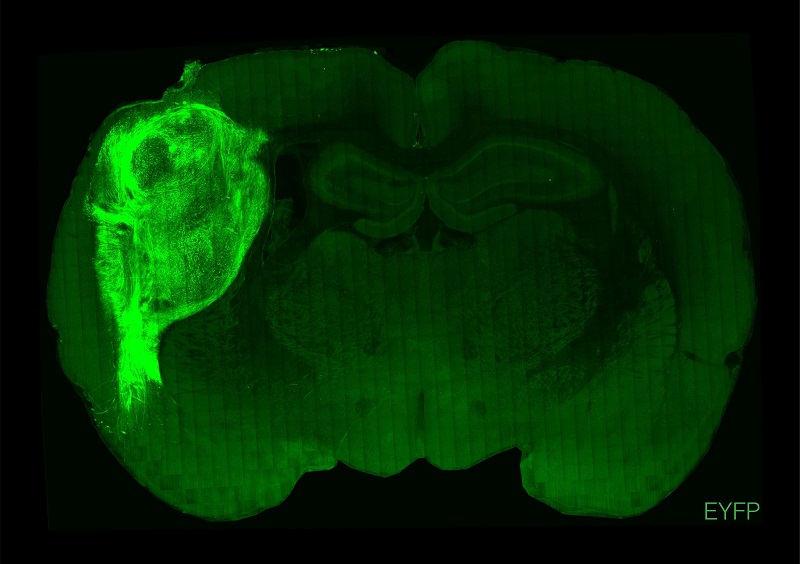

用熒光蛋白標記的人類類腦在大鼠的大腦中。

圖片來源:斯坦福大學

美國斯坦福大學研究團隊此次將人腦類器官植入新生大鼠大腦的體感皮層中,體感皮層是負責從全身接收和處理感覺信息的腦區,包括觸覺。他們發現,該類器官能發育成熟,部分能與神經環路整合,并在大鼠大腦中具有功能性。這種整合讓研究人員能在人細胞的活動與動物習得行為之間建立關聯,證明植入的神經元可以調節大鼠的神經元活動,并能誘導追求獎賞的行為。